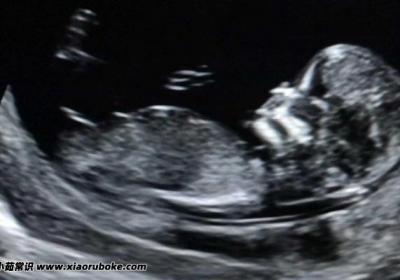

NT三個亮點是男孩女孩,網傳說法為男孩(概率總結的規律),NT三個亮點是男孩女,孩,網傳說法為男孩(,概率總結的規律)...